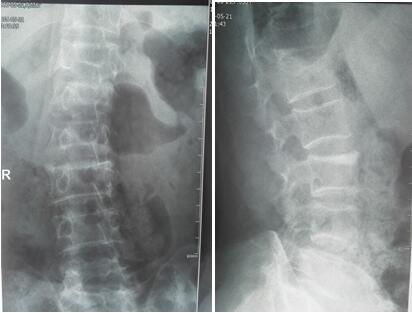

术前正侧位X线片